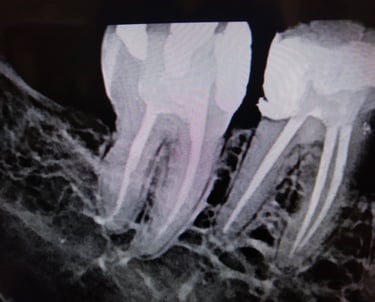

Condutos Radiculares

Os condutos radiculares(canais) limpos garantem um maior índice de sucesso na endodontia.

Casos complexos onde há calcificações/obliterações na entrada do conduto. Essa guia vence esse obstáculo liberando o canal para uma desinfecção e uma endodontia de qualidade.

Canais Obturados